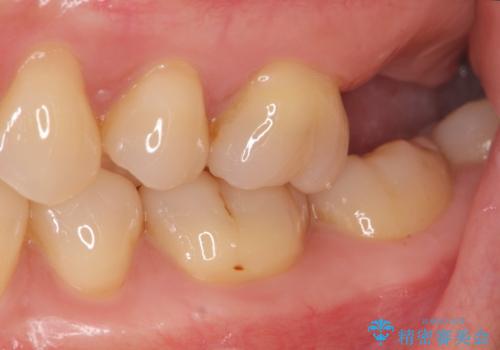

噛むと歯が疼く 歯牙破折からのインプラント治療

- 噛むと歯が疼いて痛い、と根管治療を希望され来院されました。

精査した結果、上顎奥歯は歯が割れてしまっており、根管治療ではなく抜歯の対象でした。

歯の抜去後、しっかりと咬合機能を回復するためインプラントを用いた治療を行っていきます。

歯の破折で抜歯を余儀なくされ、ショックが大きかったですが、しっかりとインプラントで咬合機能が回復することができ、喜んでいただくことができました。